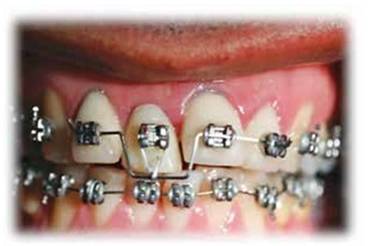

Se coloca una corona temporal de policarboxilato y se cementa.Se colocan brackets y un alambre de nitinol con un doblés a nivel de 1.1 para realizar tracción. (Figura 9)

Figura 9:  Se colocan brackets y un alambre rectangular de 17 x 25 de nitinol con un doblés a nivel de 1.1 para realizar tracción coronal.